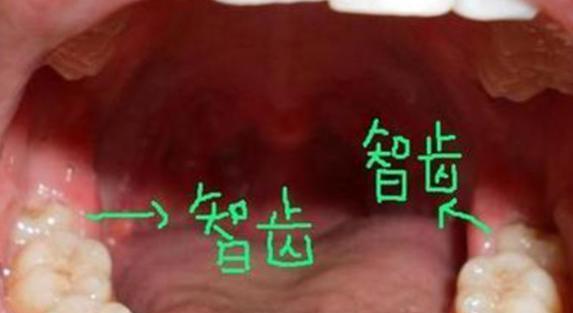

022、智齿

不管男人还是女人 , 很多人都有智齿 , 这样会给身体造成很大的伤害 , 拔智齿的过程中也会很疼痛 , 拔完以后会出现脸肿的情况 , 很多人还会呕吐 , 对身心造成很大的打击 , 但是拔掉智齿以后不会影响身体 , 也不会影响正常的生活 。